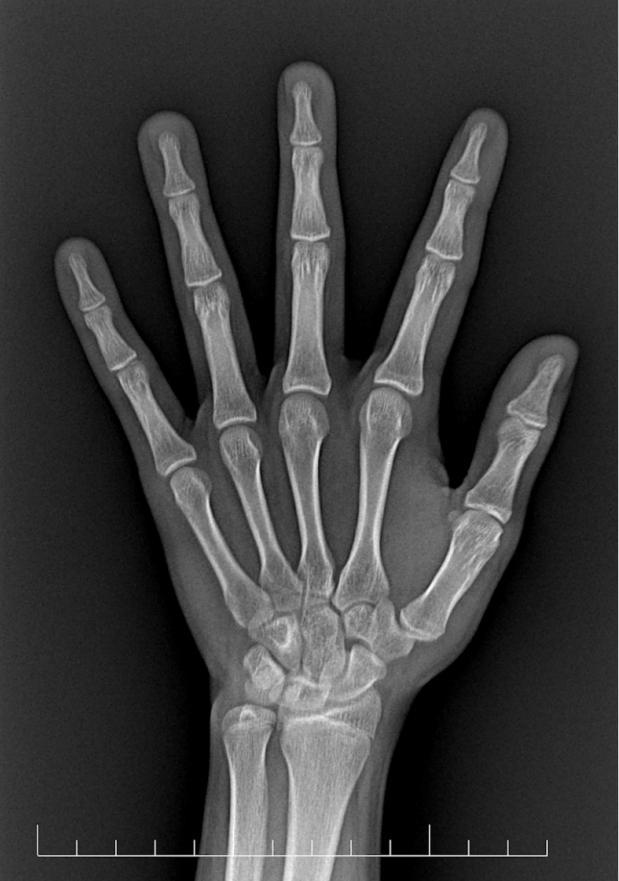

等拿到骨龄评估报告,孩子父亲沉默了,骨龄提示小杨已超16岁,骨骺接近闭合,生长空间所剩无几。孩子长到170cm的梦想,瞬间成为泡影。父亲懊悔不已:“要是早点继续监测,早点干预,结果会不会不一样?”

什么是骨龄?简单说,就是骨骼的“身份证年龄”。每个孩子都有两个年龄:生活年龄:从出生那天算起,过了几个生日就是几岁;骨骼年龄:骨骼实际发育成熟的程度。这两个年龄本该步调一致,但现实中却常常“错位”。就像小杨,生活年龄14岁,骨骼年龄却已跑到16岁,提前“成熟”了。

有些孩子看似长得快(像两年前的小杨),但可能是骨龄跑得更快,生长周期缩短,最终反而长不高。有些孩子长得慢,但骨龄也慢,反而有“后发优势”。只关注身高不关注骨龄,就像只看车速不看油表,可能突然发现“没油了”,但为时已晚。